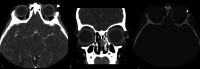

The lacrimal gland is a bilobed serous gland located in the superolateral aspect of the orbit. Lacrimal system pathologies can be broadly divided into pathologies of the lacrimal gland and those of the nasolacrimal drainage apparatus. These include distinct congenital, infectious, inflammatory, and benign, indeterminate, and malignant neoplastic lesions. Trauma and resultant fractures affecting lacrimal drainage apparatus is not part of this review; only non-traumatic diseases will be discussed. CT is the initial modality of choice because of its ability to delineate lacrimal system anatomy and demonstrate most lacrimal drainage system abnormalities and their extent. It also assesses bony architecture and characterizes any osseous changes. MRI is helpful in further characterizing these lesions and better assessing involvement of the surrounding soft tissue structures. In this pictorial review, we will review the anatomy of the lacrimal system, describe CT/MRI findings of the common and uncommon lacrimal system abnormalities and discuss relevance of imaging with regards to patient management.